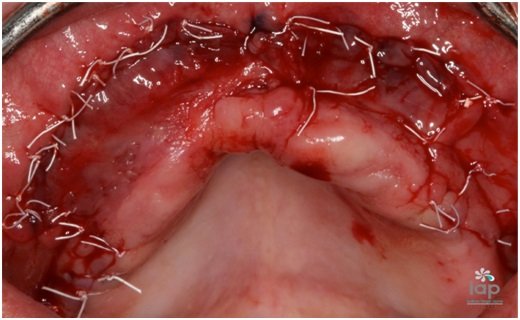

Após conversar e analisar as opções de tratamento, optou-se pelo uso do rhBMP-2 (Infuse Bone Graft, 5,6 cc, Medtronic Sofamor Danek USA, Inc), associado ao beta tricálcio fosfato (Bone Ceramic, partículas 500- 1.000 micrometros, Straumann, Basel, Suíça) e telas de titanio (Titanium Augmentation Micro Mesh – 120 x 60mm e parafusos,Ace Surgical Supply Co.,Inc)